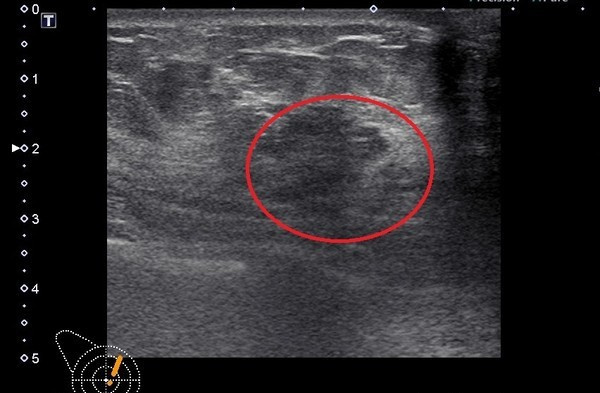

乳房钙化点是乳癌的其中一种表现型式,也就是说,钙化点不等于是乳癌,乳癌患者也不一定会出现钙化点。钙化点形成的原因,通常是乳腺里面液体分泌,这些液体中含有钙成分,由于密度极高,不透光而形成小白点。

要分辨钙化点为良性或恶性,医生会观察钙化点的形状和分布来判定。良性钙化点在影像学上的特色是均匀分布、有对称性,通常两边乳腺都有;形状也较为规律,例如圆形、爆米花状、茶杯状等等。